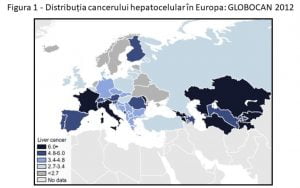

Cu toate acestea, spre deosebire de scăderea ratelor de deces pentru majoritatea cazurilor de cancer, ratele de deces prin cancer hepatic au crescut cu 2% pe an, din 2007 până în 2016, devenind a doua cauză de deces prin cancer în SUA, în timp ce sunt endemice în unele țări, inclusiv Franța, Italia și România .